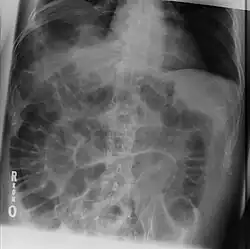

A radiologic sign is an objective indication of some medical fact (that is, a medical sign) that is detected by a physician during radiologic examination with medical imaging[1] (for example, via an X-ray, CT scan, MRI scan, or sonographic scan).